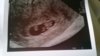

DSC_0473.JPG

Mój maluszek :)